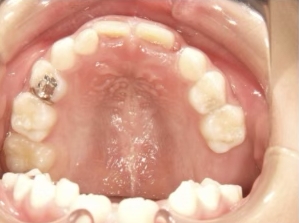

治療中⑨ 中3:14y4m

モノブロック装置で左上八重歯が改善しました

今後、必要によりマルチブラケット法へ移行予定です